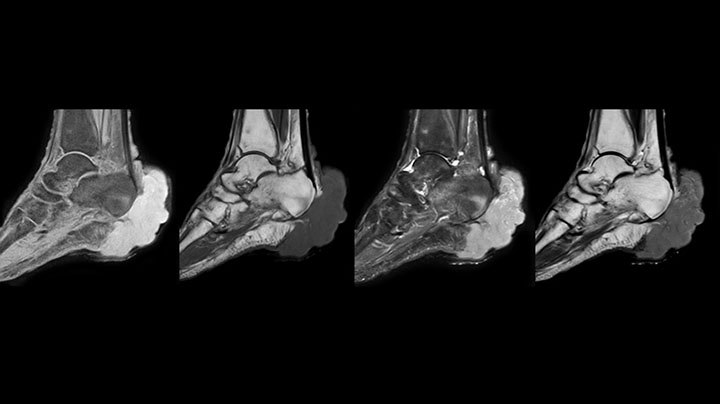

MRI examination on Prodiva 1.5T of a 72-year-old female with a malignant melanoma in the ankle. mDIXON TSE provides excellent fat suppression, without the distortion that is often seen at such extremities.